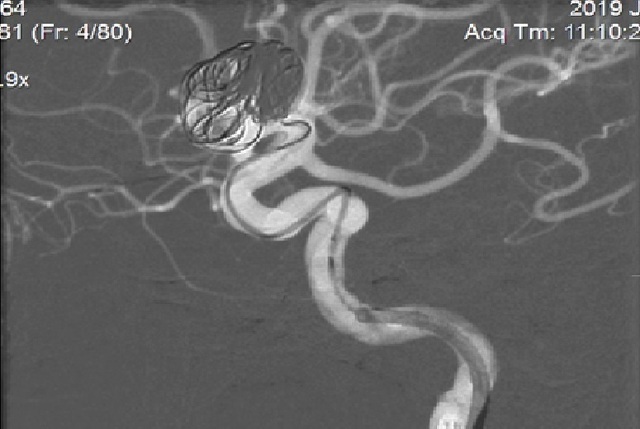

Hình ảnh túi phình đã tắc sau can thiệp, dòng chảy vào túi phình khổng lồ động mạch cảnh trong phải đã giảm gần hoàn toàn sau đặt stent chuyển dòng, khởi phát quá trình lấp dần để tắc túi phình hoàn toàn.

Sau can thiệp, bệnh nhân tỉnh, tiếp xúc tốt, huyết động ổn định, có thể xuất viện ngày hôm sau. Ê-kíp mổ được thực hiện với sự chỉ đạo và hỗ trợ của TS.BS. Nguyễn Trọng Tuyển (Bệnh viện Trung ương Quân đội 108), Th.s. Lê Vũ Huỳnh, Th.s. Nguyễn Viết Quý và ê-kíp can thiệp mạch não của Khoa Đột Quị, với sự gây mê của khoa Gây mê Hồi sức Tim mạch, Bệnh viện Trung ương Huế. Hiện bệnh nhân đang chờ để được xuất viện.